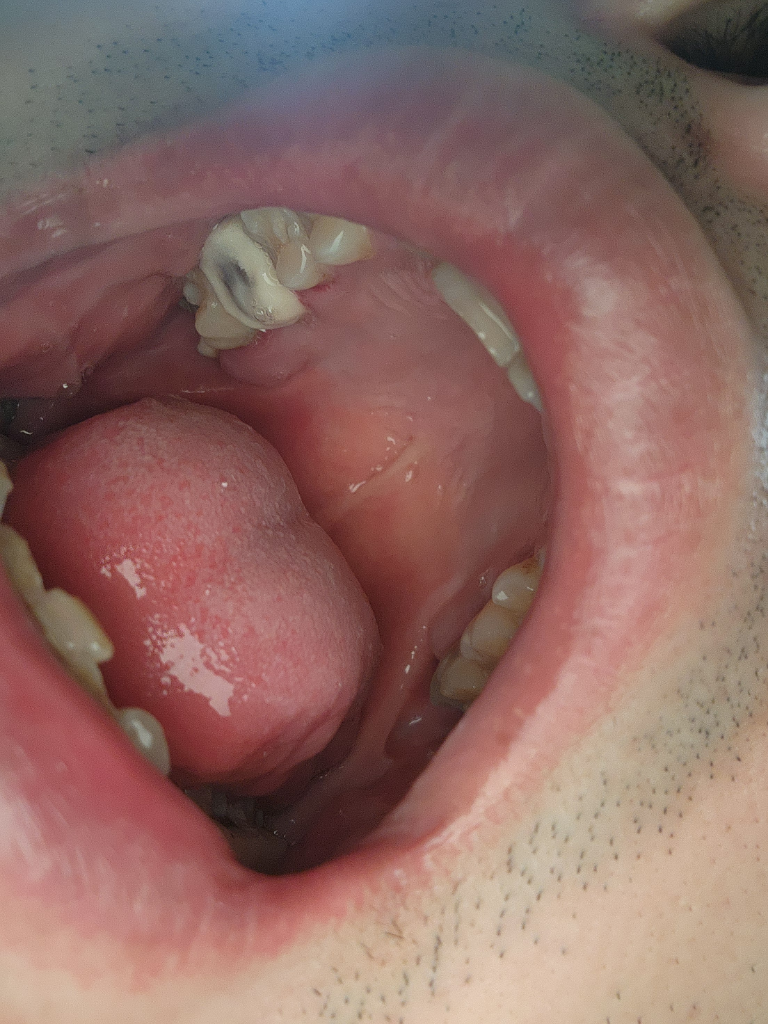

임시치아 안에 검은색 질문드릴게요

임시치아 안에 검은색이 붙여 있는데 저게 레진이 맞을까요? 레진비는 청구햇지만 저 검은색이 레진으로 때운건지 모르겟어요 알려주세요

• 1번 째 사진

사진으로는 정확하게 확인이 되지는 않지만 임시 치아가 얇다면 내부에 보이는 재료가 비춰 보여서 어둡게 보이는 경우가 있습니다.

저부위는 검은색이라기 보다는 임시치아가 얇아서 안쪽 치아가 비춰 보이는거 같습니다. 레진은 안쪽에 신경치료후에 단단하게 치아를 떄우셧을꺼에요.

1. 임시치아가 얇아 안쪽이 비쳐보이는 것 같습니다. 임시치아는 맞물리는 치아와 거의 닿지 않게 해두기 위해 씹는면을 다듬다보면 아주 얇은 상태일 수 있습니다.

2. 레진의 경우 신경치료 후 코어를 쌓았다면 코어레진비용일 것입니다.